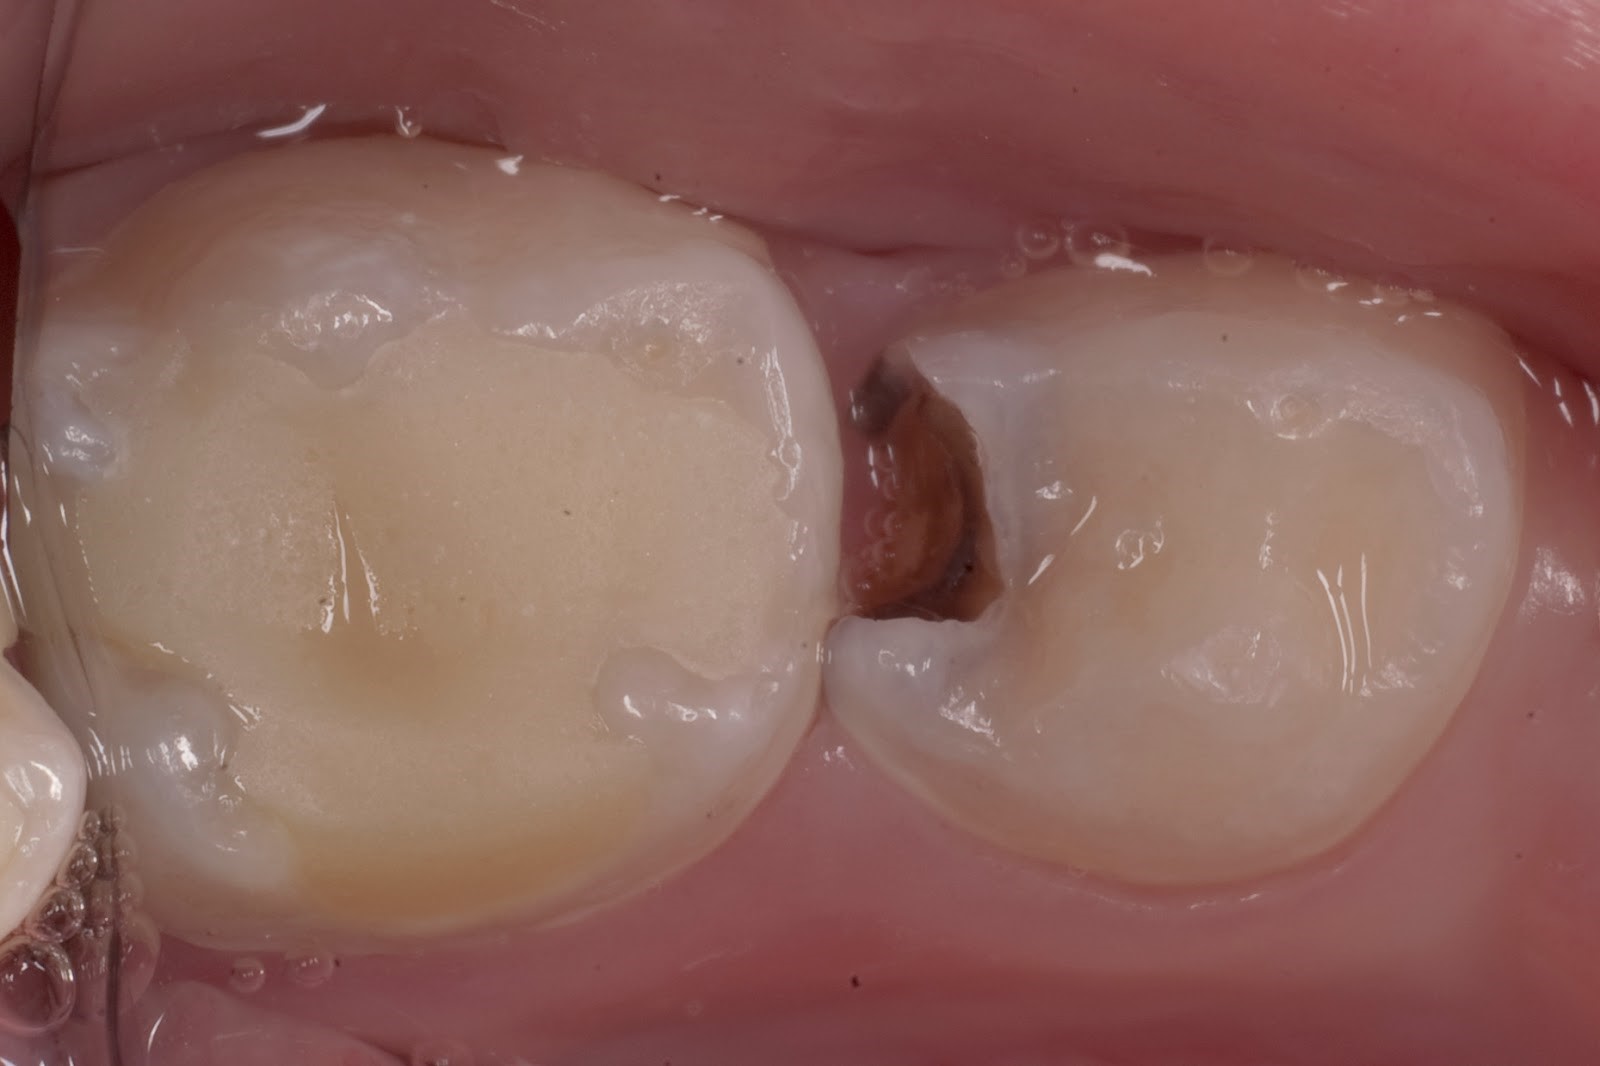

Фото

Средний кариес — распространенная стоматологическая проблема. Лечение обычно проходит быстро и безболезненно: стоматолог удаляет поврежденные ткани и заполняет полость пломбой. Регулярные посещения стоматолога помогают рано выявить кариес и избежать серьезных осложнений.

Специфическая локализация для кариеса – это жевательные зубы в области контактной поверхности, фиссуры (особенно располагающиеся на внутренней стороне). Размягчается только верхний и средний уровни тканей, поэтому прогноз благоприятен.